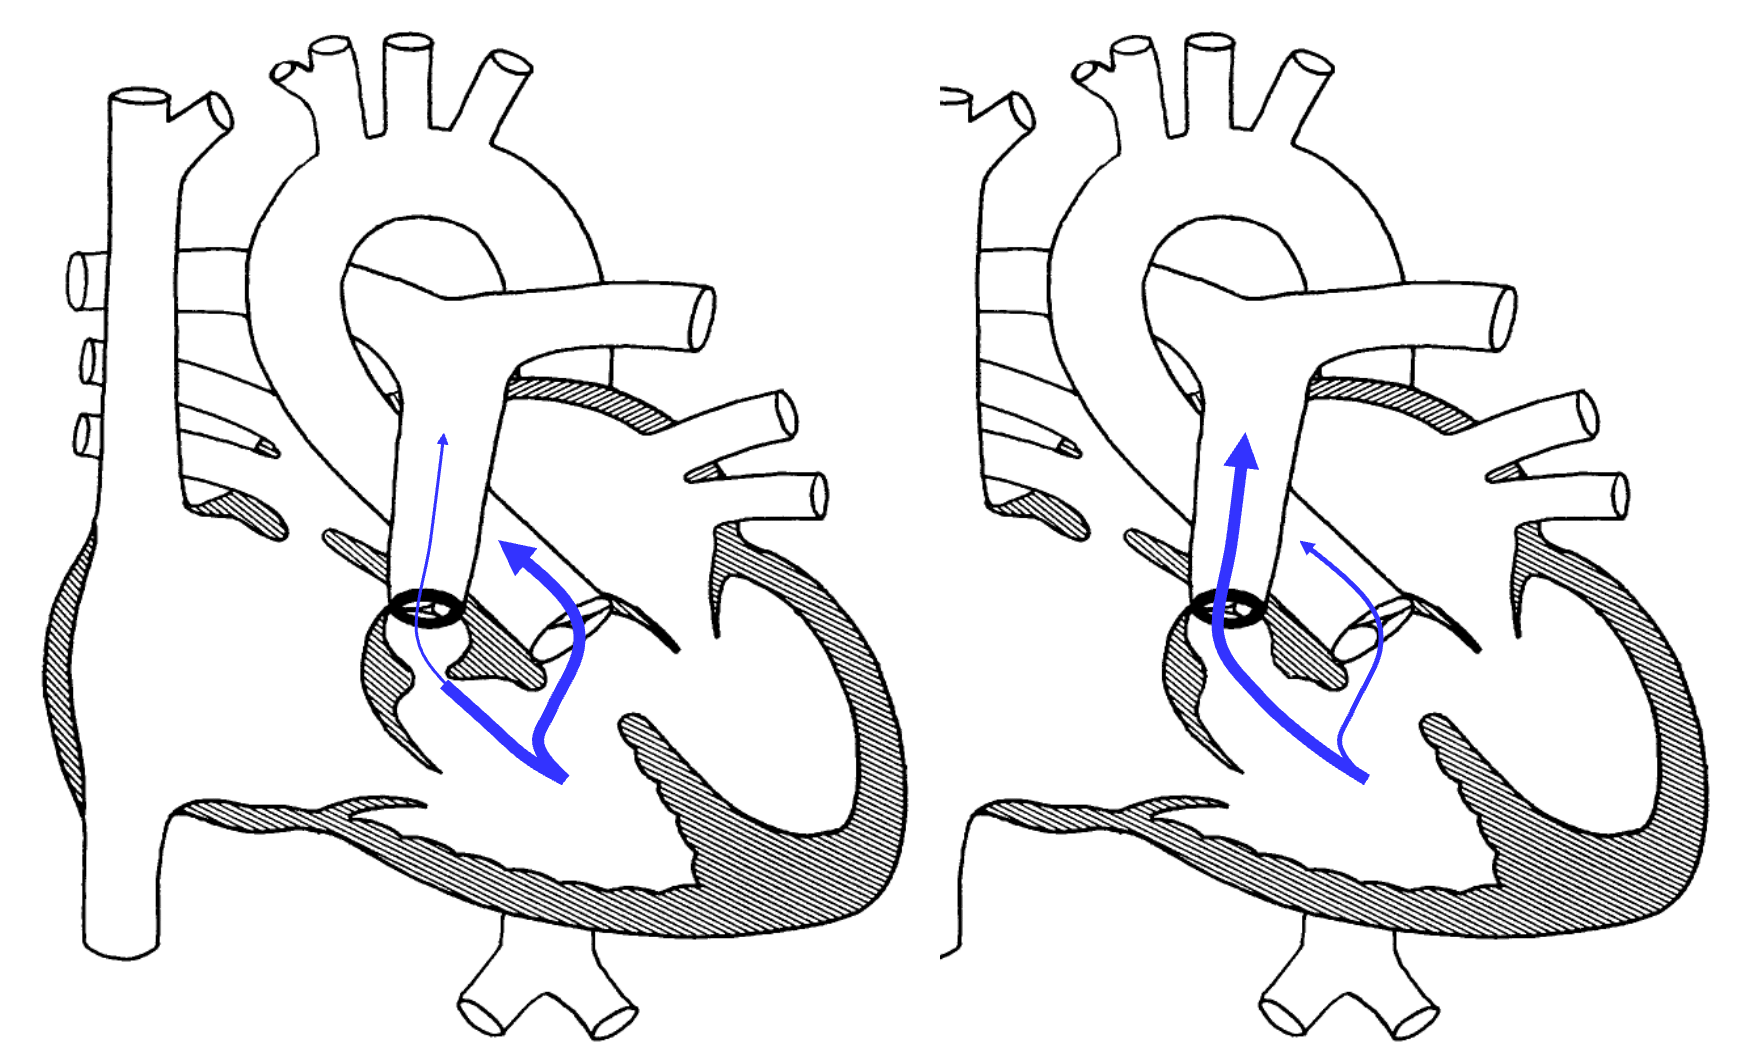

Transposition of the Great Arteries

- Although dextroposed transposition of the great arteries represents only about 5% of congenital heart defects, it is the most common cyanotic lesion to present in the newborn period.

- A history of cyanosis is always present, although it depends on the amount of mixing. Tachypnea and a single S2 are typically present. If the ventricular septum is intact, there may be no murmur.

- Children with transposition and a large VSD have improved intracardiac mixing and less cyanosis. They may present with signs of heart failure. The heart is hyperdynamic, with palpable left and right ventricular impulses. A loud VSD murmur is heard. S2 is single.

- D-TGA:

- PDA is needed for proper mixing of pulmonary and systemic circulations.